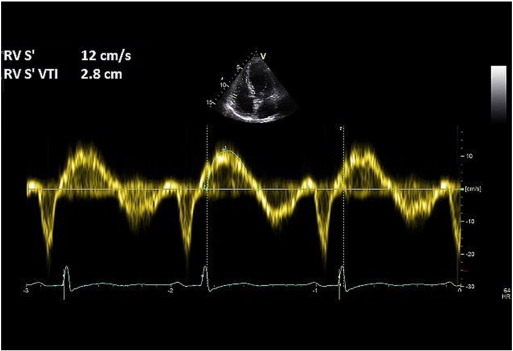

Tissue Doppler imaging (TDI) is used on the RV free wall in the apical 4-chamber view, and tricuspid annular systolic myocardial (Sm ) velocity is recorded. The maximal Sm velocity and the Sm VTI are then measured (Fig. 6 ). Sm velocity < 12 cm/s and Sm VTI < 2.5 are highly suggestive of elevated PASP [23] .

Fig. 6. RV tissue Doppler method for assessing pulmonary pressure. |

This method correlates well with TR measured PASP but is yet to be fully validated against the gold standard-invasive right heart catheterisation [23] and [24] . Although the technique helps to identify patients with pulmonary hypertension, it cannot accurately quantify pulmonary artery pressure.